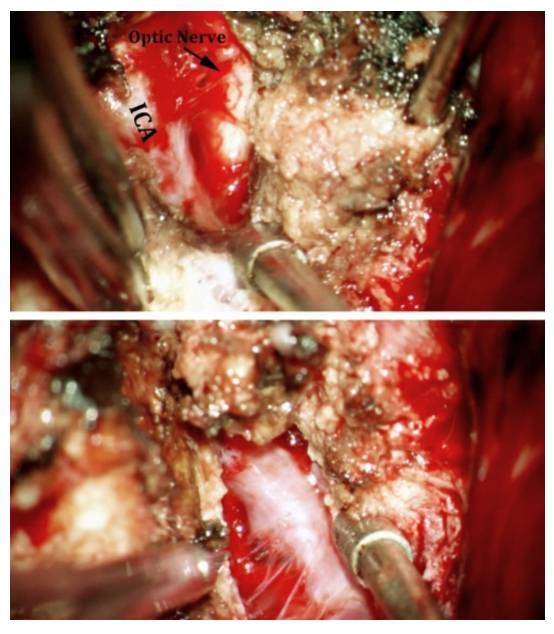

图12. 仔细地将肿瘤前极游离出来,对于识别位于颅底的视神经和ICA是非常重要的(上图)。沿着蝶骨翼内侧走形,可以大致定位视神经管和ICA。在下方的图片中,术中将肿瘤的前额部切除后,吸引器尖端所对的就是视神经和颈内动脉的位置。电凝后残留的肿瘤组织位于天幕边缘。

图17. 该蝶骨嵴内侧脑膜瘤的纤维样包膜很难松动,最后将肿瘤沿着ICA的长轴分为两半,才得以切除。首先在颅底识别颈动脉近端和视神经(上图)。然后将肿瘤沿着ICA的长轴切开(下图),这样有利于松动肿瘤,并最终将肿瘤的前后两部分切除。